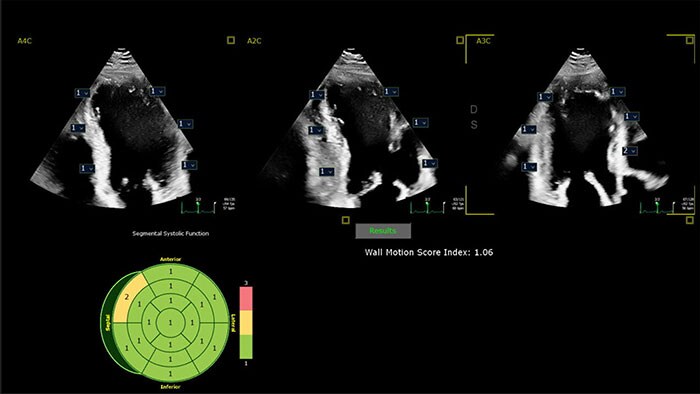

Powered by AI-based capabilities, our industry-leading CV ultrasound platform delivers advanced tools for structural heart disease, including 3D automated tricuspid valve and color flow quantification tools. Efficient automation and quantification tools enable you to diagnose heart failure and coronary artery disease quickly and confidently. Tiny transducers, high frame rates and sharp imaging support confidence in pediatric echo exams. Unified on- and off-cart workflow supports lab setup and consistent UI and workflow across systems.

Philips AI-based ultrasound solutions integrate into everyday clinical workflows and are designed to make it easier and faster for clinicians to acquire, select, measure and report accurate results.